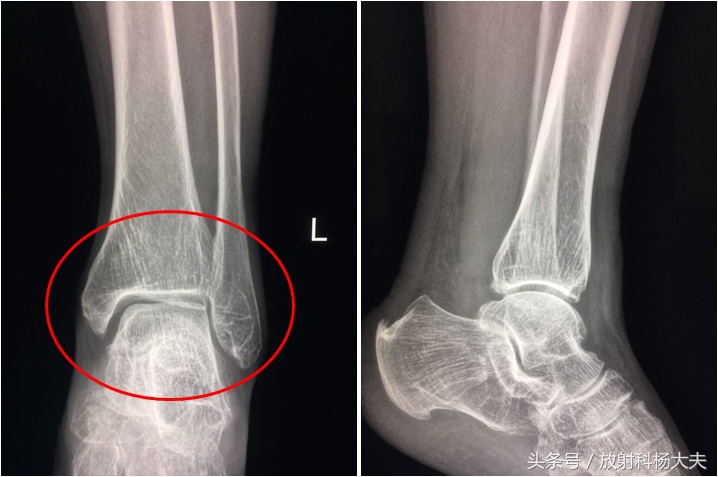

没有骨折,只有轻度的退行性骨关节病